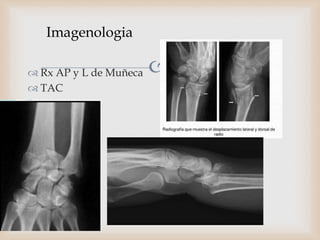

Imagenologia

 Rx AP y L de Muñeca

 TAC

 La evaluación radiográfica incluye proyecciones antero-posterior

(AP), lateral (L) y oblicua que deben mostrar la extensión y

dirección del desplazamiento inicial.

 Tras la reducción cerrada deberán repetirse las radiografías para

identificar la deformidad residual y el grado de conminución.